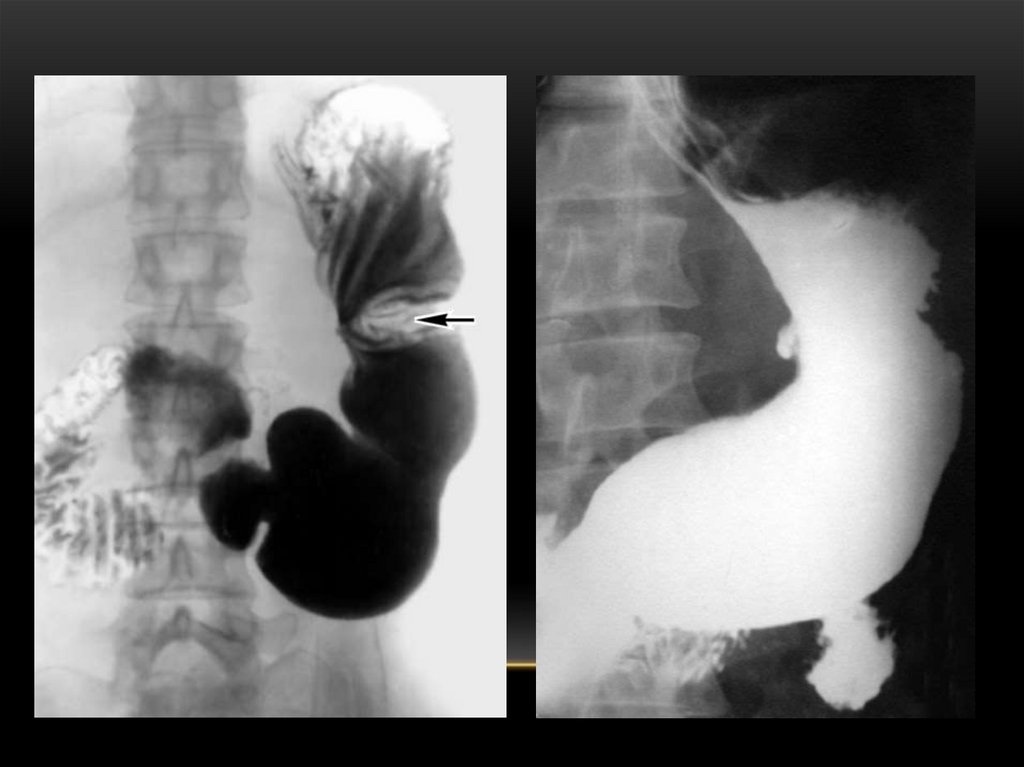

АСҚАЗАННЫҢ ОЙЫҚ ЖАРА АУРУЫ

Асқазан шырышты қабаты дефекті